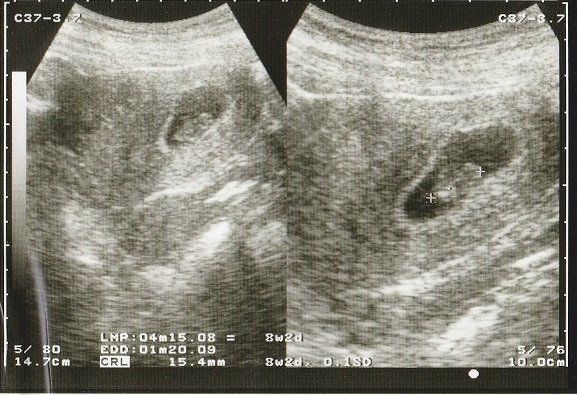

妊娠9週目のエコー写真 何となく人の形?

落花生のように真ん中がくびれた胎児の形が見えるようになってきました。